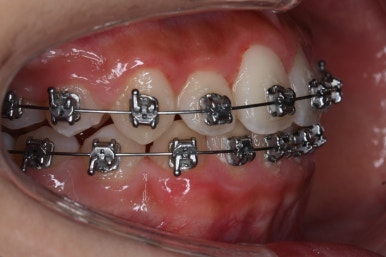

다른 앵글에서의 모습입니다.

안으로 쏙 들어가 있던 앞니가 앞으로 나오게 되면서 심미적으로 좋아지는 것을 볼 수 잇습니다.

악궁확장장치는 유지기간 이 후 다 제거가 되었고, 치아들이 매우 가지런해지는 것을 볼 수 있습니다.

이제 조금만 더 정리가 되면 장치 제거가 가능하겠네요.